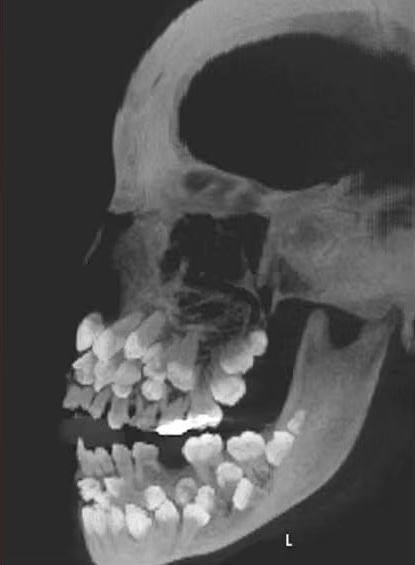

根據媒體《Chosun Biz》的報導,《美國齒顎矯正與顏面矯形學期刊》2011年曾刊登一起罕見病例,巴西一名11歲女童因想拔除一顆上排乳牙就醫,起初牙醫進行口腔檢查時並無異狀,誰知在照完X光後醫生大驚失色,因為女童嘴裡竟藏了18顆乳牙、32顆恆牙,以及31顆多生牙,一張小嘴共擁有多達81顆牙齒。

據了解,一般成人的正常牙齒數量為32顆,額外長出的牙齒被稱為「多生牙」,通常多生牙數量不會超過2顆。但女童足足有超過30顆多生牙,情況實屬罕見,醫療團隊進一步為女童做遺傳檢測,這才發現她第9對染色體中出現「染色體倒位」的異常結構,也就是部分染色體片段呈現反轉,或許就是造成她多生牙爆量的原因。

多生牙有的會深埋在牙齦內,有的外觀也與正常牙齒無異,雖然靠肉眼無法察覺,但很可能會阻礙正常牙齒生長或牙齒排列混亂,甚至引發囊腫等其他併發癥,貿然拔除還可能損傷顎骨。醫療團隊因此集結了牙周、矯正、口腔外科、贋復等專家,為女童訂定長期治療計畫,盼能安全處理這些多出來的牙齒。